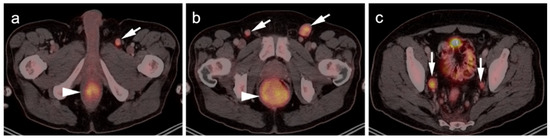

- Mankia, S.K.; Miller, R.F.; Edwards, S.G.; Ramsay, A.; Lee, S.M. The Response of HIV-Associated Lymphadenopathic Kaposi Sarcoma to Highly Active Antiretroviral Therapy Evaluated by 18F-FDG PET/CT. Clin. Nucl. Med. 2012, 37, 692–693. [Google Scholar] [CrossRef]

- Morooka, M.; Ito, K.; Kubota, K.; Minamimoto, R.; Shida, Y.; Hasuo, K.; Ito, T.; Tasato, D.; Honda, H.; Teruya, K.; et al. Whole-body 18F-fluorodeoxyglucose positron emission tomography/computed tomography images before and after chemotherapy for Kaposi sarcoma and highly active antiretrovirus therapy. Jpn. J. Radiol. 2010, 28, 759–762. [Google Scholar] [CrossRef]

- Polizzotto, M.N.; Millo, C.; Uldrick, T.S.; Aleman, K.; Whatley, M.; Wyvill, K.M.; O’Mahony, D.; Marshall, V.; Whitby, D.; Maass-Moreno, R.; et al. 18F-fluorodeoxyglucose Positron Emission Tomography in Kaposi Sarcoma Herpesvirus–Associated Multicentric Castleman Disease: Correlation with Activity, Severity, Inflammatory and Virologic Parameters. J. Infect. Dis. 2015, 212, 1250–1260. [Google Scholar] [CrossRef] [Green Version]